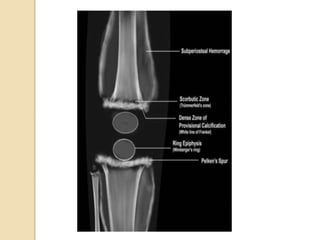

WHITE LINE OF FRENKEL

 Dense zone of

provisional calcification.

 Radiodense line in the

zone of provisional

calcification at the

growing metaphysis

 Cause- Cartilage

proliferation decreased

with normal

mineralisation.

Conversion into bone is

delayed.

TRUMMERFELD ZONE

(Scorbutic zone)

 Transverse radiolucent

band directly beneath

the zone of provisonal

calcification.

 Cause- Suppressed

osteoblastic activity

mineralisation leading

to disordered osteoid

formation.

 Trabecular bone mass is

decreased.

PELKAN’S SPUR

 Bony protuberances at

the metaphyseal

margins at right angles

to the shaft.

 Cause- Zone of

provisional calcification

extends beyond the

margins of the

metaphysis resulting in

periosteal elevation

and marginal spur

formation

WIMBERGER'S

SIGN

(Ring epiphysis)

 Epiphysis is small &

sharply marginated by

sclerotic rim with central

portion more radiolucent.

 Cause- Decreased

cartilage proliferation

and unimpaired

mineralization

(sclerosis)

 Differentiates healing

rickets and scurvy